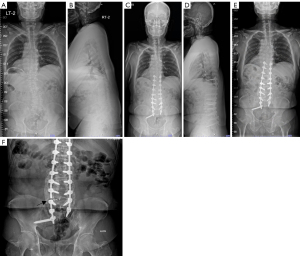

The 2-year postoperative fusion rate was 95% (76/80) (Table 3). The overall complication rate was 21% (17 patients), including four cases of S1 screw loosening, two cases of PJK, six cases of rod breakage (Figure 2) and three cases of S2AI screw-related pain. Two re-operations (3%) were performed due to rod breakage (Figure 3), resulting from loss of reduction following the fracture.